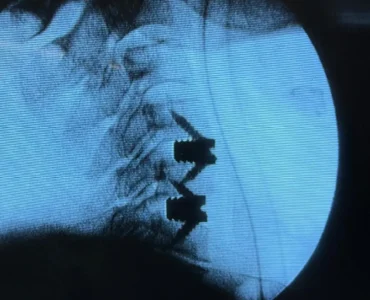

Imagine feeling an electric shock in your jaw every time you speak or eat. This patient was suffering from Trigeminal Neuralgia, experiencing severe "current-like pain" in her lower jaw.

The Challenge & Solution:

Complex Case: The patient was immunocompromised, meaning major open surgery was too risky.

Minimally Invasive Solution: We chose Radiofrequency Ablation (RFA). Using a specialized needle guided by live X-ray imaging, we targeted the V3 nerve branch causing the pain.

Immediate Relief: The procedure was a success! The "current" pain resolved immediately, leaving the patient pain-free and recovering comfortably.

At The Brain & Spine Centre, we offer advanced, non-surgical options for chronic pain relief. You don`t have to live with the pain!